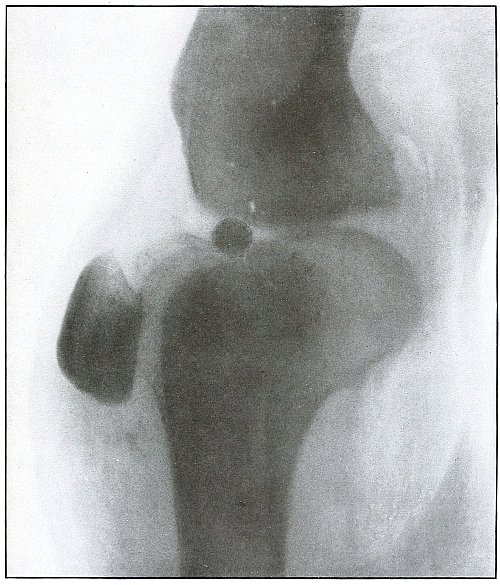

Plate 48.

_

[Pg 107]

Rifle—Plate 48.

LOWER EXTREMITY.

Gunshot Wound of the Thigh,

with Lodgment of the Bullet.

Wound of entrance, outer aspect of the thigh at the junction of the upper and middle thirds.

The slight penetration without bone injury and with slight deformity of the nose of the bullet indicates that the wound was caused by a ricochet shot at extreme range, after its energy was almost spent.

With the posterior aspect of the thigh next to the plate, the dense shadow and the nearly normal size of its outline indicate that the bullet was in the same relative position and that it lay posterior to the neck of the femur.

As such wounds are rarely infected, the treatment is conservative, and a search for the missile is only justified by serious infection, pain, or impaired function. [Pg 108]